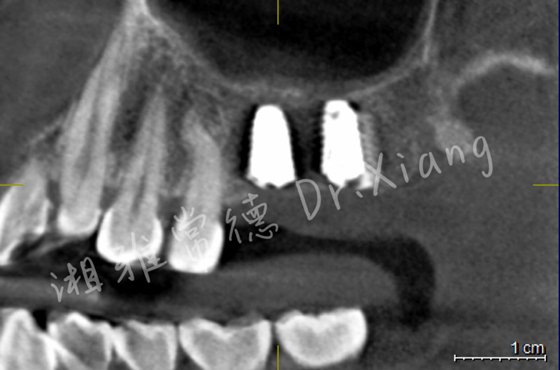

經(jīng)過9個月骨愈合后,患者復查錐形束CT,骨愈合十分滿意。9月中旬,向峰醫(yī)師種植團隊成功為患者實施了第二步的手術,取出內(nèi)固定裝置的同時為患者成功微創(chuàng)的植入2枚種植體,完成了患者左上頜區(qū)域的軟硬組織的自然恢復和改建。

種植體精準微創(chuàng)植入